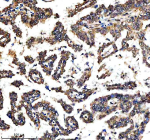

Immunohistochemical staining of RTRAF using anti-RTRAF antibody. RTRAF was detected in a paraffin-embedded section of human colon cancer tissue. Heat mediated antigen retrieval was performed in EDTA buffer (pH 8.0, epitope retrieval solution). The tissue section was blocked with 10% goat serum. The tissue section was then incubated with 2 ug/ml rabbit anti-RTRAF antibody overnight at 4oC. Peroxidase Conjugated Goat Anti-rabbit IgG was used as secondary antibody and incubated for 30 minutes at 37oC. The tissue section was developed using an HRP secondary and DAB substrate.